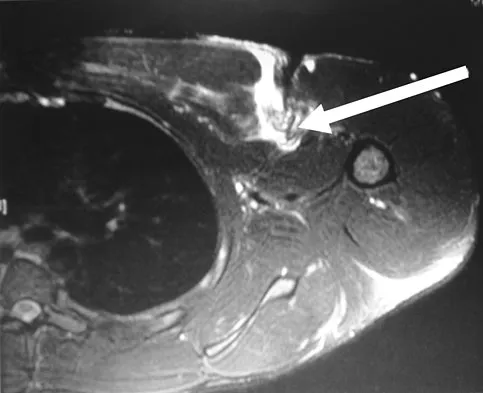

Figures 13a and 13b show the MRI scans of a 70-year-old patient who has a posterior calf mass. Examination reveals that the mass extends to the midcalf level. A biopsy specimen reveals a high-grade soft-tissue sarcoma. Metastatic work-up shows no lesions. Management should consist of

Explanation